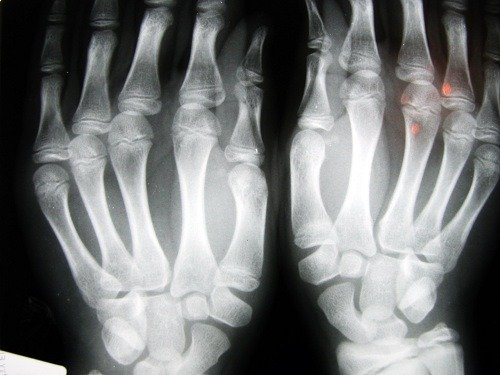

Som nevnt, er det en skjelettsykdom. Den forårsaker en nedgang i tetthet av beinmassen, og er karakterisert av porøse ben. Ved å øke størrelsen på de indre cellene i beinene, blir de sprø og brekker lettere.

Beinbrudd oppstår ofte i håndleddene, og også i hoften. Dette er det mest alvorlige bruddet fordi det involverer et umiddelbart kirurgisk inngrep og alvorlige konsekvenser for pasientens helse.